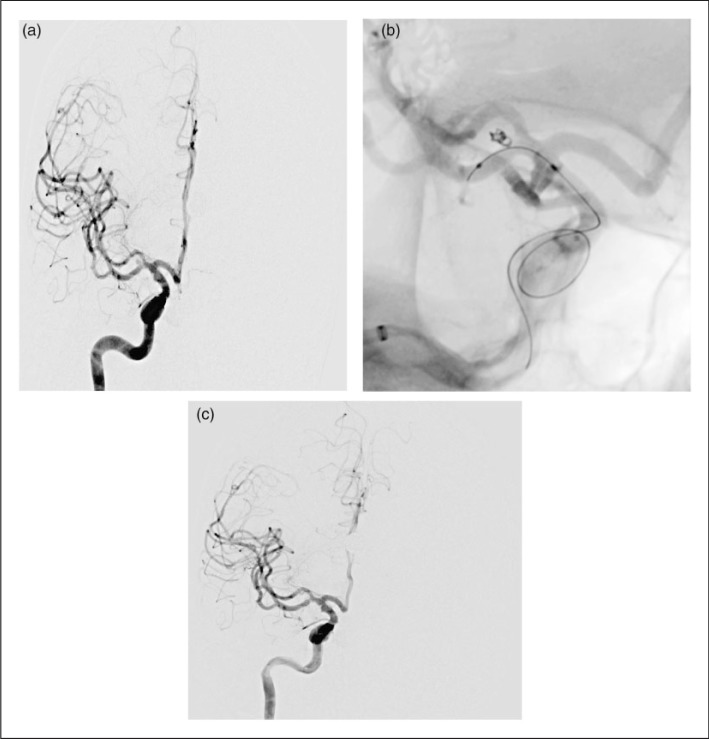

小于3mm的腦動脈瘤介入治療:微彈簧圈栓塞治療預后如何?

自20世紀90年代早期開始,血管內(nèi)栓塞顱內(nèi)動脈瘤已經(jīng)成為開顱手術和手術夾閉之外的的一種成熟和成功的替代方法。根據(jù)較近的報道,小的和小的顱內(nèi)動脈瘤被認為從血管內(nèi)的角度...